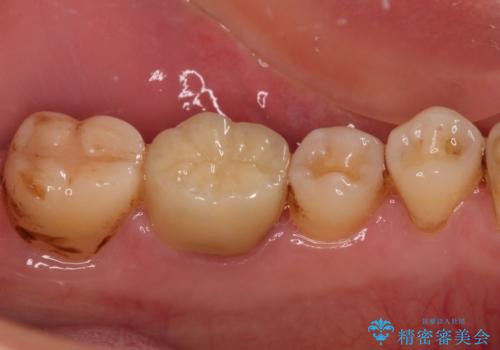

フルジルコニアクラウンは、やや光沢のある材質ですが、奥歯に装着した場合にはさほど気にならず、自然な口元の印象となりました。